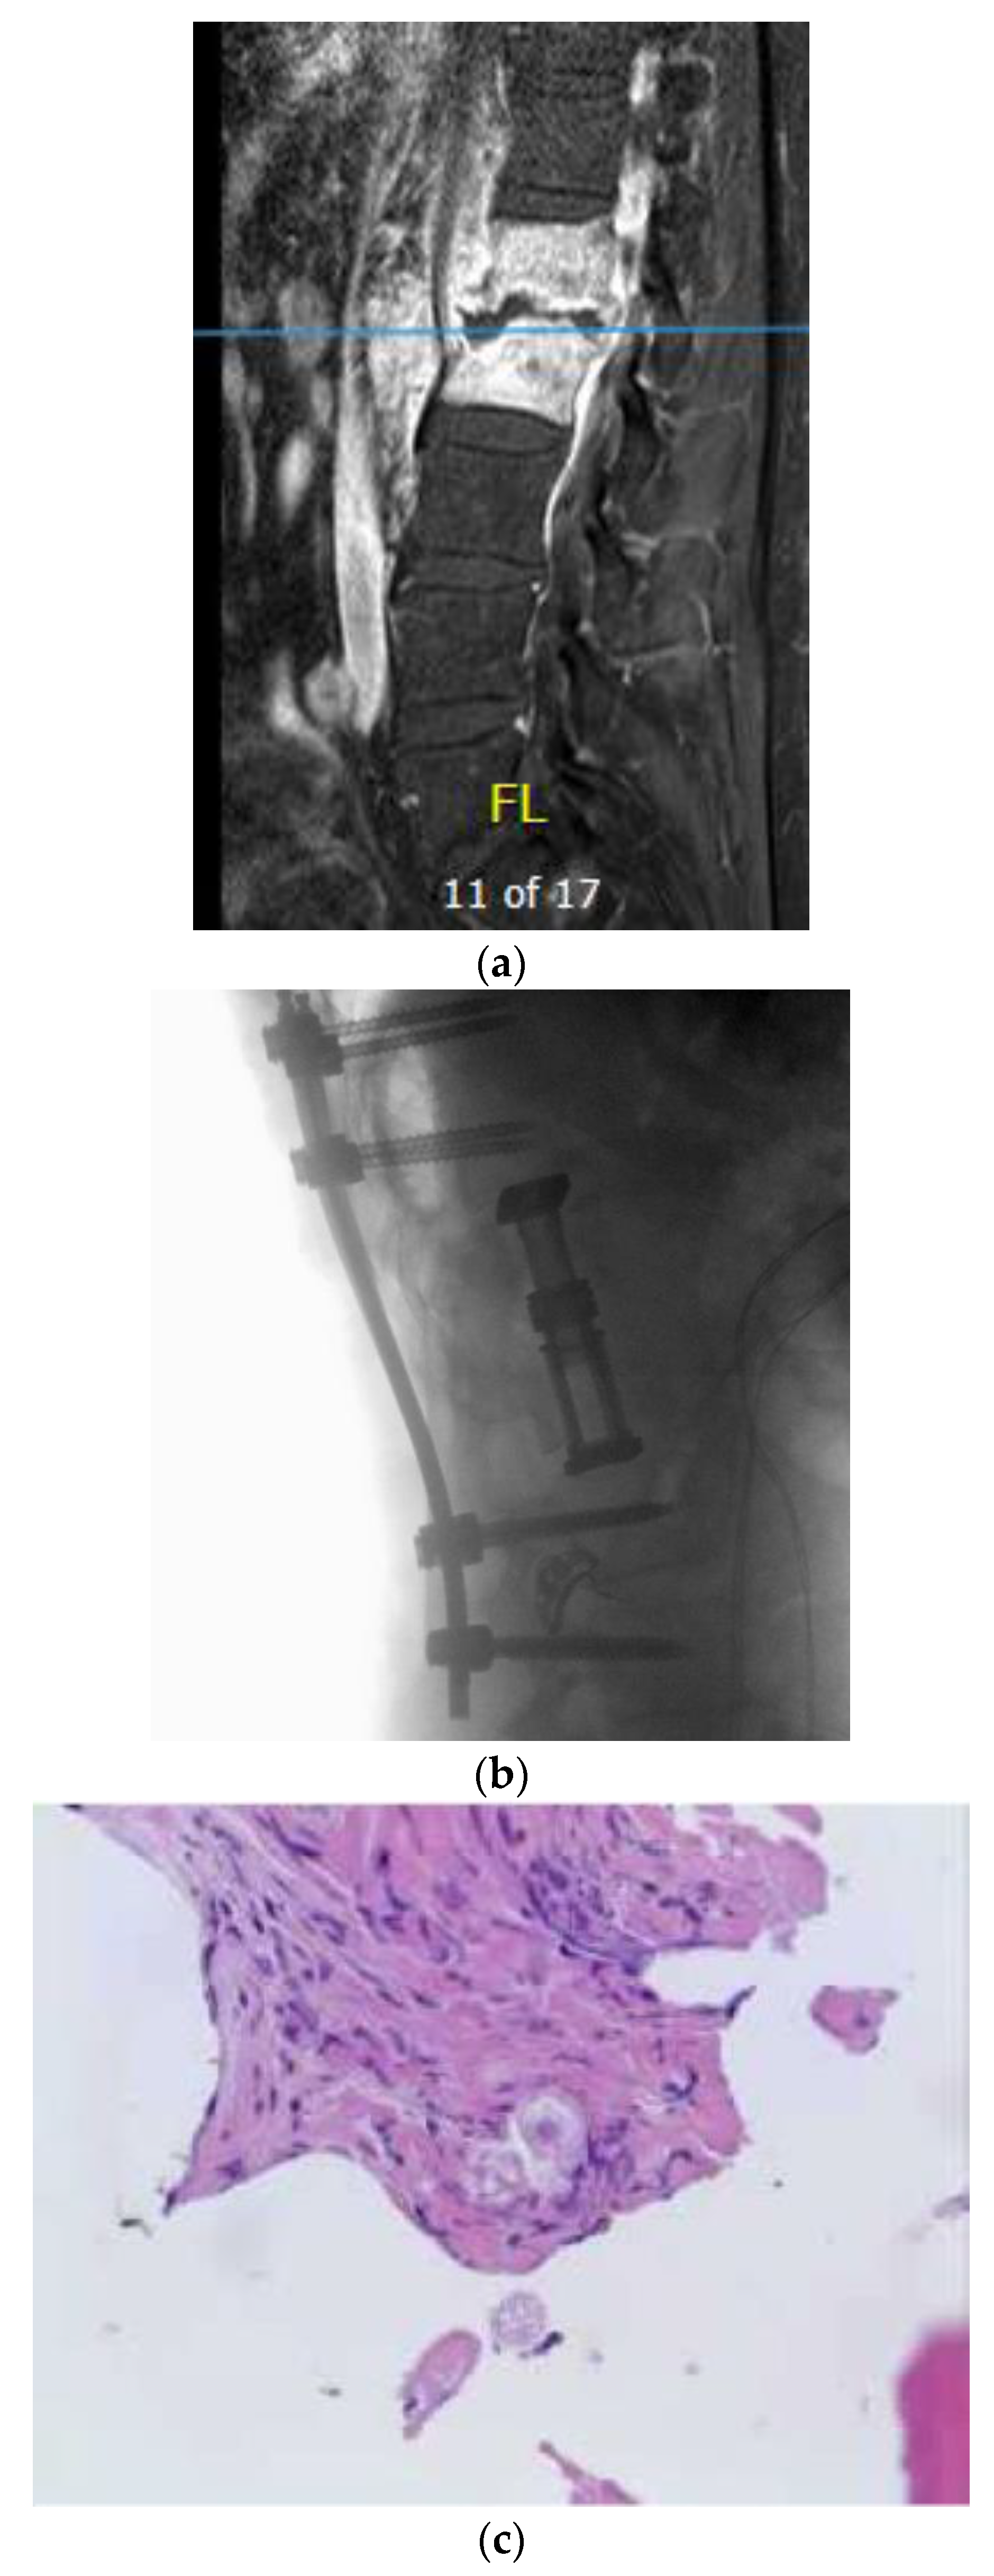

A 62-year-old man with past medical history of pulmonary fungal infection presented with a seven-month history of back pain. He was initially diagnosed with coccidioides pneumonia seven years ago and was placed on a fluconazole long-term treatment, which was later discontinued by another physician due to renal adverse effects. He presented with symptoms of severe lower back pain, which exacerbated when sitting or lying down. The symptoms of pain were associated with weakness in the lower extremities and poor balance while walking. He had chronic non-radiating back pain. MRI of the lumbar spine revealed L1–2 discitis and osteomyelitis with a paraspinal abscess (Figure 2a). Antibiotics therapy and fluconazole were started preliminarily. An image-guided interventional biopsy demonstrated coccidioidomycosis infection. Neurologically, having motor deficits and severe pain with imaging confirming compression of neural elements warranted surgical treatment. A lateral approach to the lumbar spine was undertaken to perform corpectomy of the L1 and L2 vertebral bodies along with discectomy and insertion of an expandable cage with a morselized bone graft. This construct was reinforced with a posterior instrumented fusion extending two segments superiorly and inferiorly (Figure 2b). The intraoperative specimen showed coccidiodes spherules within the bone specimen, consistent with dissemination of the infection to the spine (Figure 2c).

Figure 2. (a) Sagittal T1-weighted MR images with contrast showing extensive disc space destruction at L1–2 with epidural enhancement. (b) Sagittal T–L junction X-ray showing postoperative changes with a L1–2 corpectomy and instrumented fusion. (c) H&E staining of the intraoperative vertebral body specimen demonstrating the spherules within bone indicating osteomyelitis.